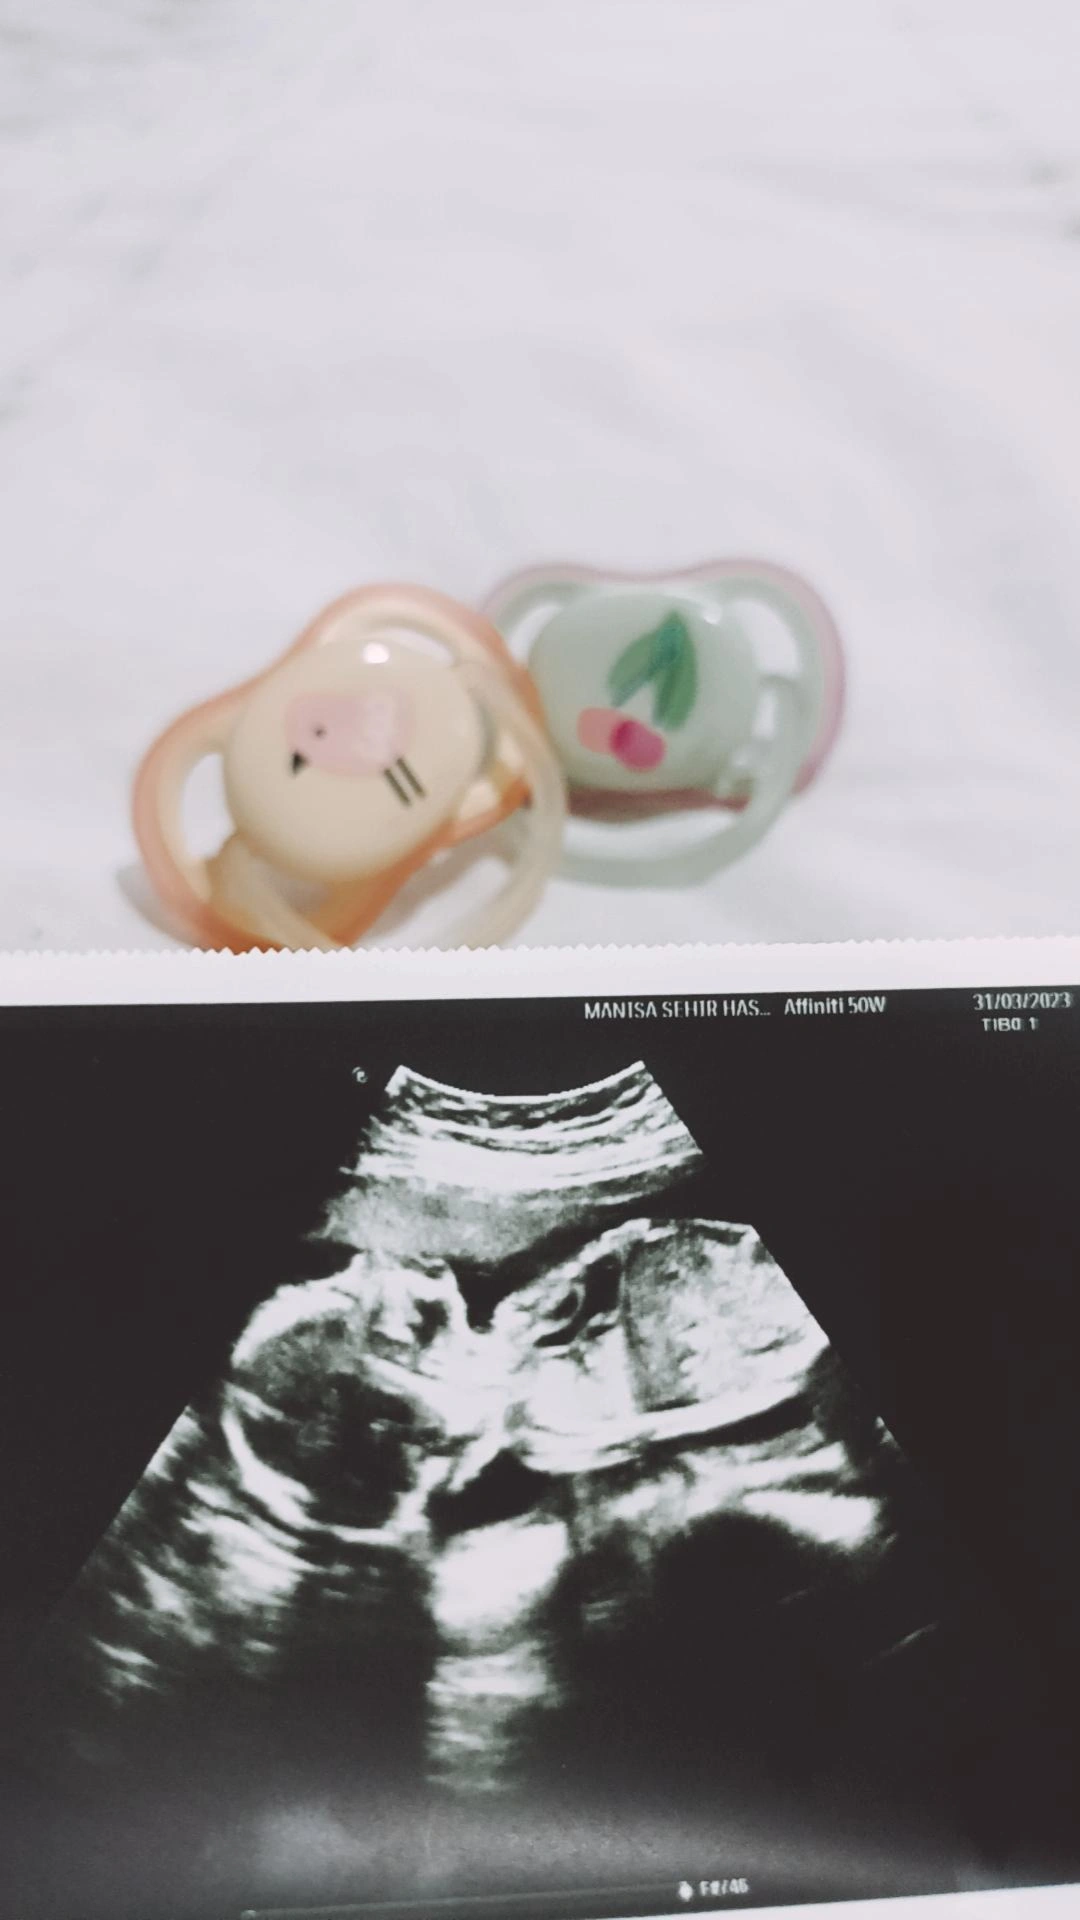

ramziye göre kıza benzettim canım